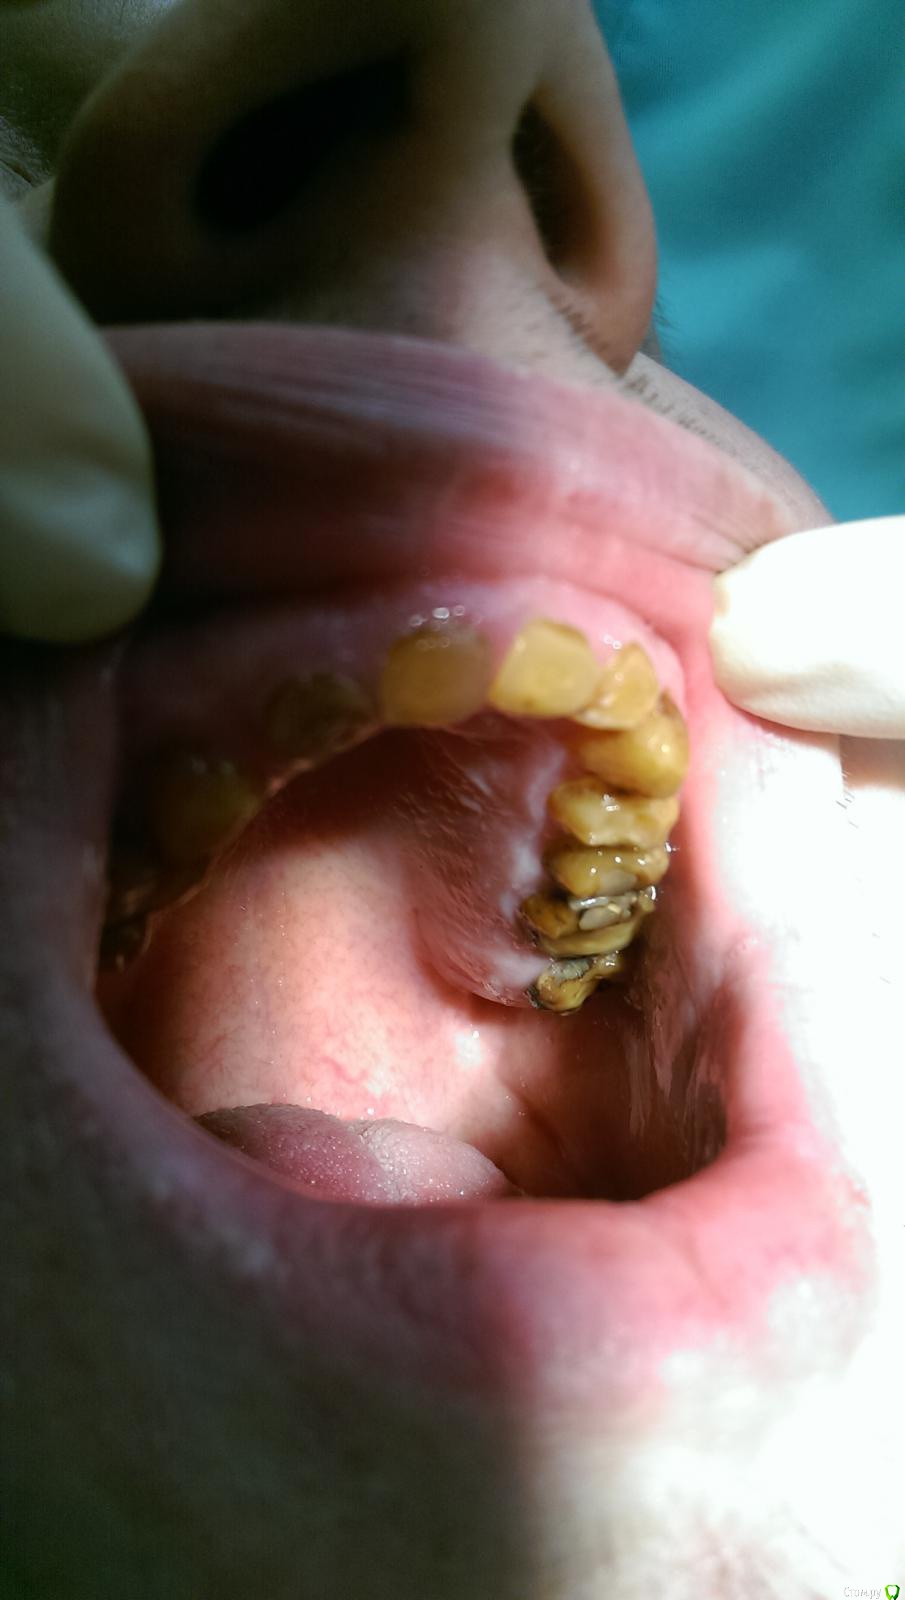

Ром@н Опубликовано 17 декабря, 2014 Поделиться Опубликовано 17 декабря, 2014 Пациент- молодой человек 28 лет.Посоветуйте пожалуйста как быть. Сегодня сфотографировал. ОПТГ будет позже - не знаю только когда, т.к. проподает. Сегодня удалили 1.6. Ссылка на комментарий

DR.P Опубликовано 19 декабря, 2014 Поделиться Опубликовано 19 декабря, 2014 (изменено) Интересный случай. Напишу краткий протокол лечения и варианты:1) измеряем физ покой, и высоту его прикуса. Если разница этих значений больше 2-3 мм - стираемость - необходимо повышать прикус.2) Если 2-3 мм - значит стираемость компенсаторная, то есть с зубоальвеолярным выдвижением. В случае 1) культевые вкладки и коронки (необходимо вернуть высоту прикуса)В случае 2) хирургическое удлинение зубов, коронки Изменено 19 декабря, 2014 пользователем DR.P Ссылка на комментарий

Ром@н Опубликовано 20 декабря, 2014 Автор Поделиться Опубликовано 20 декабря, 2014 лечил у него несколько зубов по поводу кариеса - пломбы не держатся вылетают со временем, хотя когда препарирую все плотно Ссылка на комментарий

chervoncevdaniil Опубликовано 21 декабря, 2014 Поделиться Опубликовано 21 декабря, 2014 Мне кажется тут явно снижение высоты прикуса компенсировано,взгляните на мощный альвеолярный отросток.Не простая ситуация у пациента,без грамотной хирургии будет сложно Ссылка на комментарий